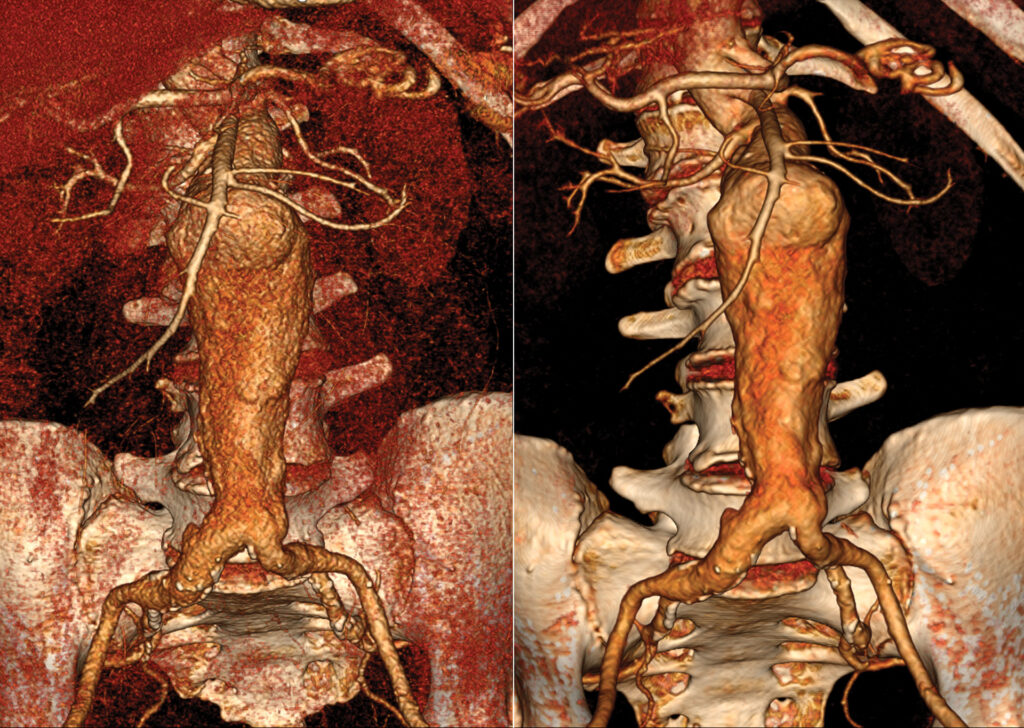

3D Printing

Converting digital medical images into 3D printed models is revolutionizing the healthcare industry. Vitrea software provides expert segmentation tools incorporated with the ability to export stereolithography (STL), OBJ (waveform object) and VRML (virtual reality modeling language) files for 3D modeling.

The 3D output anatomical model is not for diagnostic use.

Global Illumination

Global Illumination is an alternate 3D rendering technique to help provide a more photorealistic view of human anatomy. Users are able to acquire and share these images for communication and education.